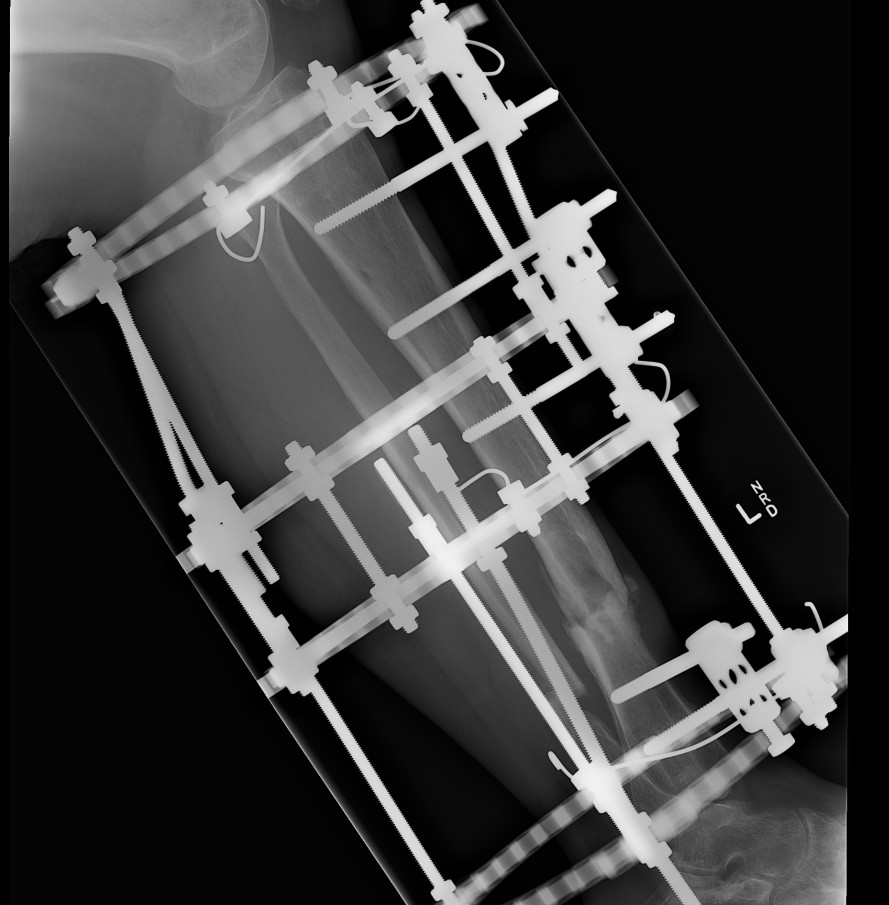

Case

12 months of persistant sinus drainage

- nail removed

- Ilizarov applied with fibular osteotomy and acute compression of non union

- 6/52 IV Abx

Infected Tibial Non Union XrayInfected Tibial Nonunion CT

Infected Tibial Non Union Ilizarov APInfected Tibial Non Union Ilizarov Lateral